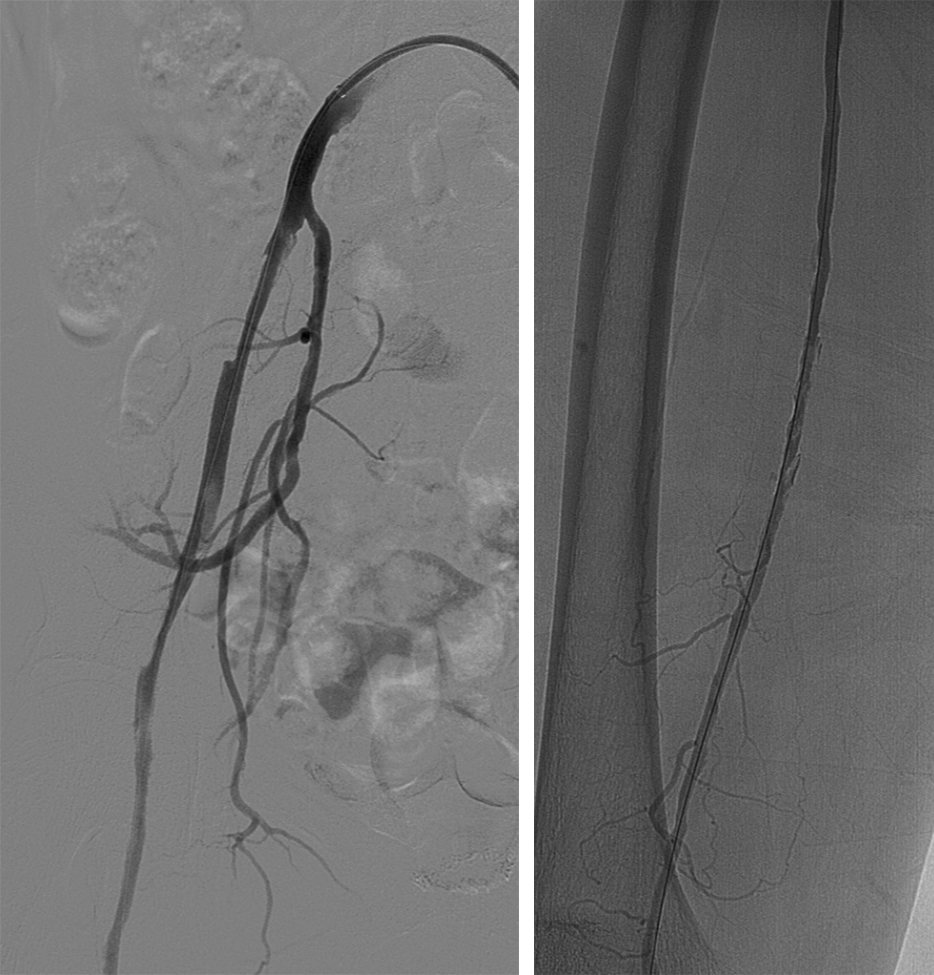

顺行穿刺无法开通,行左侧腘动脉逆行穿刺,超选进入顺行导管。

球囊扩张全程血管,显示支架内有陈旧性血栓,予6F导管吸栓,最后造影显示血流较前通畅,部分附壁血栓继续抗凝治疗,定期随诊。予Exoseal封堵穿刺点。